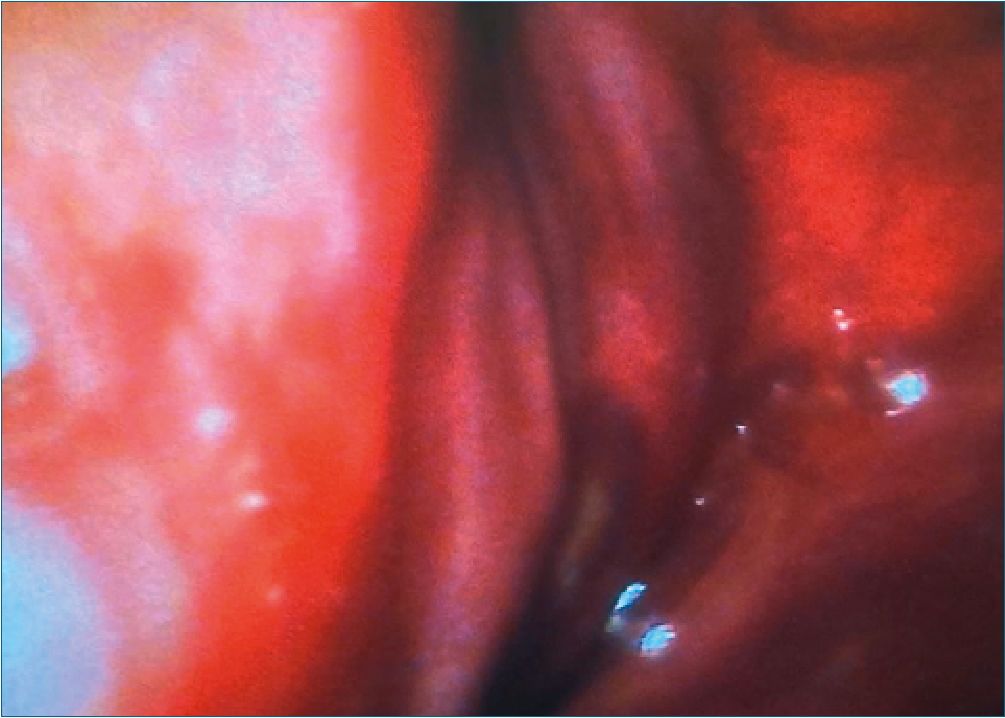

Se presenta el caso de masculino de 20 años con diagnóstico actual de intubación prolongada con neumonía por Acinetobacter baumannii secundario a dificultad respiratoria que requirió apoyo avanzado de la vía aérea, programado para traqueostomía; antecedente de seguimiento por ortopedia pediátrica debido a escoliosis neuromuscular, deformidad torácica (Figura 1 y 2), así como manchas características de “café con leche” en tórax y dorso; de manera progresiva a presentado debilidad en extremidades inferiores y múltiples internamientos por procesos neumónicos. En su valoración de predictores de vía aérea no es posible valorar Mallampati ni distancia interincisiva por la presencia de cánula orotraqueal (nnuver® 8,0 mm), protrusión mandibular no valorable, Patii Aldreti grado II (6,0 cm), distancia esternomentoniana grado IV (10 cm), Bellhouse Dore grado I, circunferencia cervical de 45 cm. Durante procedimiento anestésico se realiza monitoreo continuo tipo II; inducción con fentanilo (Kalcex®) 3 mcg/ kg, propofol (Riafol®) 1 mg/kg y cisatracurio (Lukamik®) 150 mcg/kg; se inicia modo ventilatorio tipo presión con FiO2 90%; durante el transanestesico se realiza mantenimiento con sevo- florano 2,5 Vol% alcanzando un CAM 1, línea de curva de cap- nografia presente, monitorización de relajación muscular con respuesta a tren de cuatro (TOF-Watch®). Se procede a realizar traqueostomía con observación de anillos traqueales, retirando tubo orotraqueal al momento de colocar cánula Portex® 7,5 mm, al verificar ventilación con circuito anestésico se observa ausencia de capnografia, y en la elevación de fuelle en máquina de anestesia, por lo que se decide el cambio a cánula Portex® 8,0 mm persistiendo fuga y ausencia nuevamente capnografía; por lo que se realiza nueva videolaringoscopia con Glidescope® observando epiglotitis, desviación a la izquierda de vía aérea, Cormack Lehane IV (Figura 3); por lo que de manera emergente se coloca cánula orotraqueal (nnuver® 8,5 mm) a 15 cm a través de traqueostomía identificando curva de capnografía (Figura 4), con adecuada exhalación de CO2; conservando en todo momento estabilidad hemodinámica. Decidiendo terminar procedimiento quirúrgico y continuar el mantenimiento ventilatorio a través de este dispositivo.

Figura 3. Evidencia de epiglotitis y desviación de las estructuras.